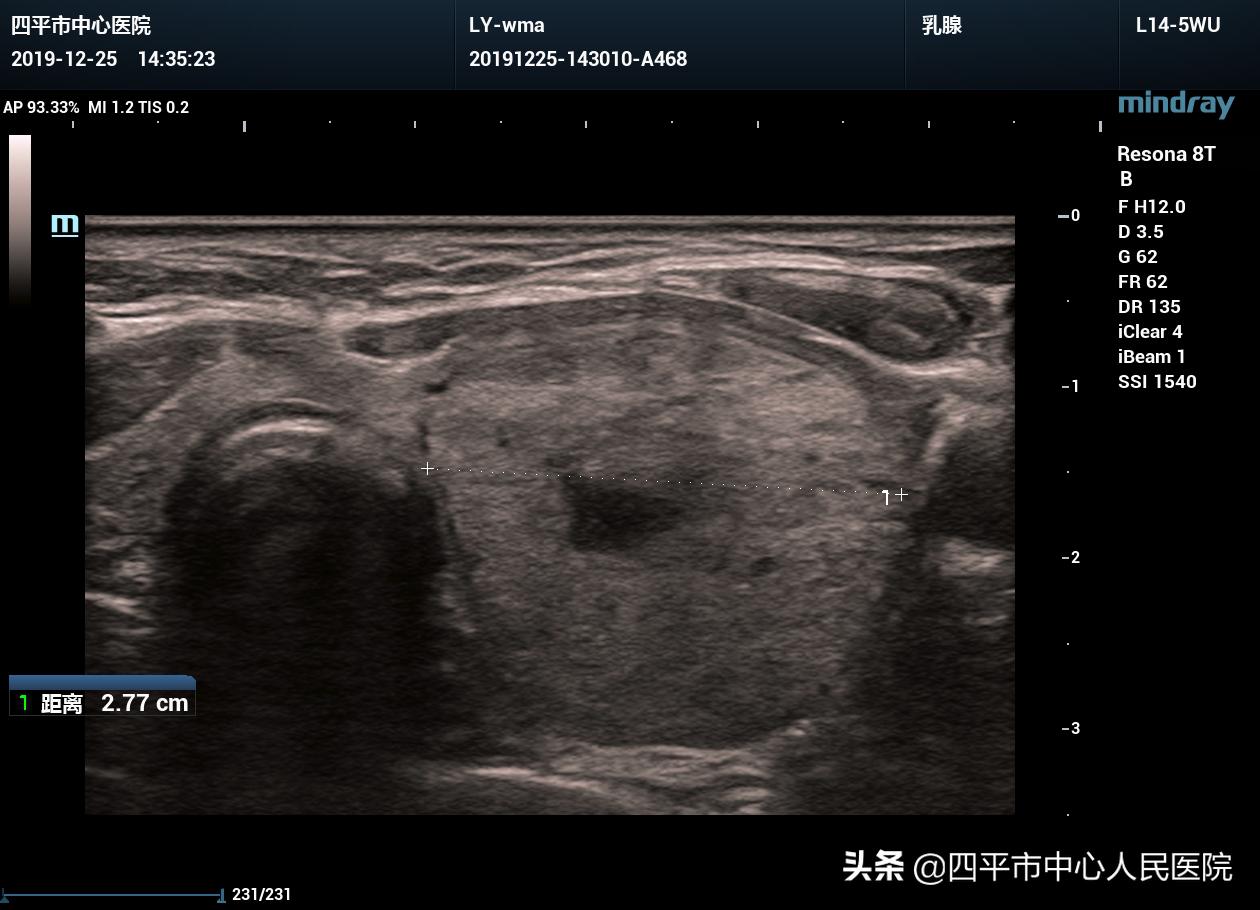

3、檢查:可能需要進(jìn)行血常規(guī)、尿常規(guī)、甲狀腺功能檢查、甲狀腺超聲等檢查,以明確結(jié)節(jié)的性質(zhì)和大小。